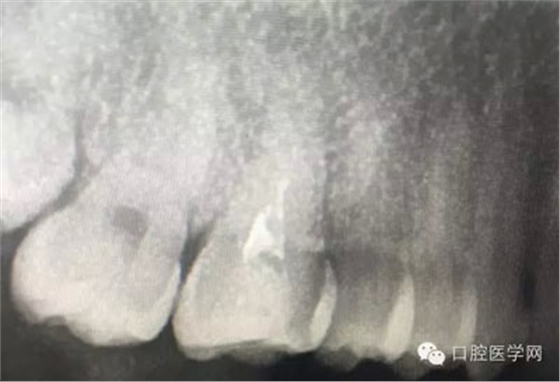

這是一例外院樹脂修復(fù)后十個(gè)月出現(xiàn)牙髓炎癥狀的患者。遇到這樣子的患者大家會(huì)怎么做,證明選擇,還有就是可做可不做治療的如何去平衡。